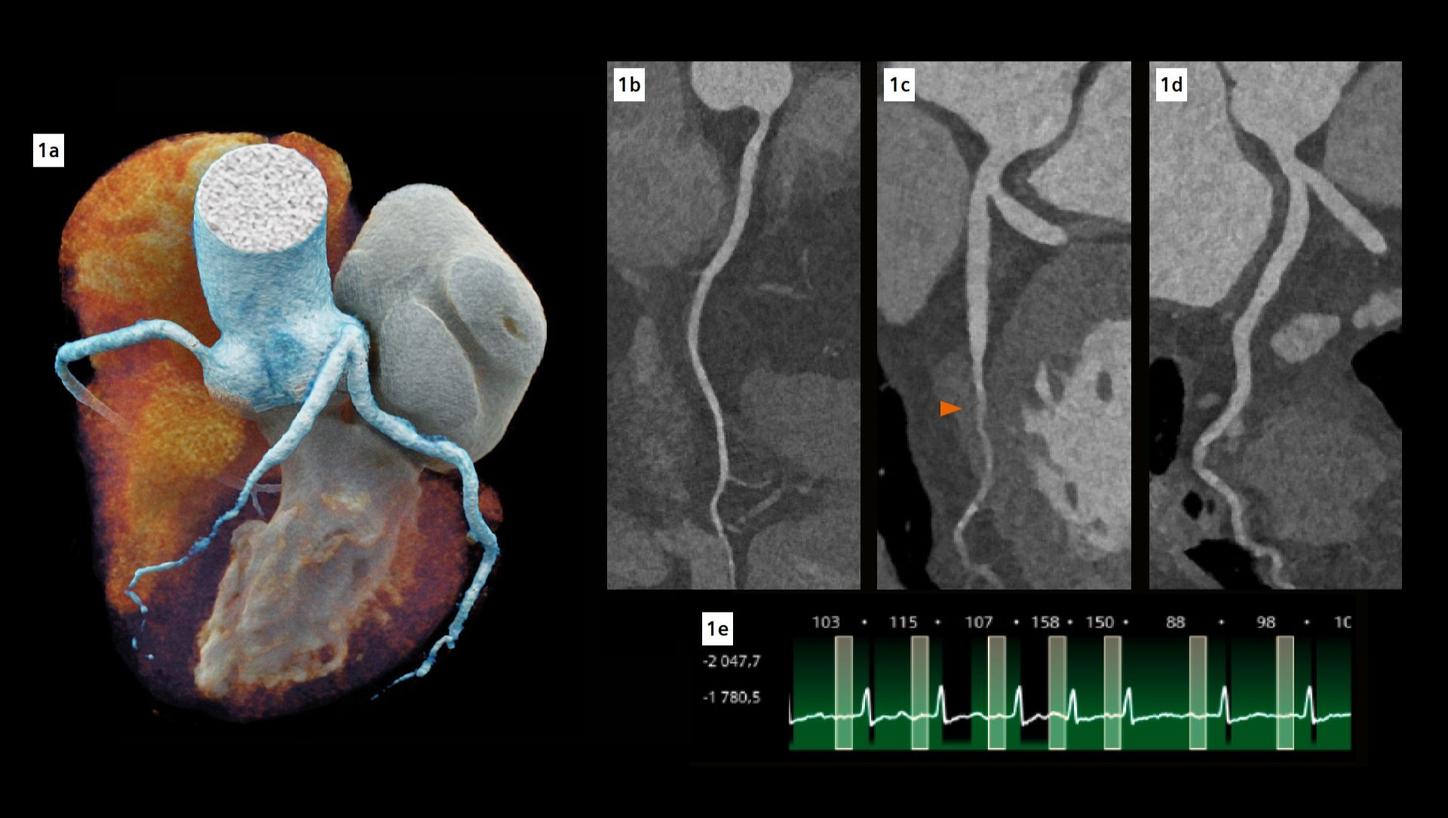

Fig. 1: Cinematic volume rendering technique (cVRT) image of the heart (a) and curved multiplanar reconstructions of the coronary arteries (b-d). (b) represents the right coronary artery, (c) represents the left main and left anterior descending (LAD) coronary artery, while (d) represents the left main and left circumflex coronary artery. The arrow indicates a complete myocardial bridge on the middle LAD. Note the excellent visualization of the coronary arteries despite high and irregular heart rate (e).

The fine spatial detail (0.4 mm slice thickness) enabled an accurate evaluation of the coronary arteries to rule out severe CAD (as part of the differential diagnosis of chest pain) (see Figure 1). The use of advanced image reconstruction algorithms, such as ZeeFree, combined with the preview series function, resulted in only minor motion artifacts on the acquired scans, despite the high heart rate variability (Minimum: 86, Maximum: 158, average: 110). Detector-based quantum spectral imaging capabilities (lung analysis reconstruction) made it impressively fast to detect lung perfusion deficits caused by the PE and aided further therapy decision-making by down-grading disease severity. A fair dose length product (636 mGy*cm) was achieved during the chest CTA, utilizing the NAEOTOM Alpha.Prime CT scanner with an optimized protocol, serving as a true “one-stop-shop” TRO-CT examination.